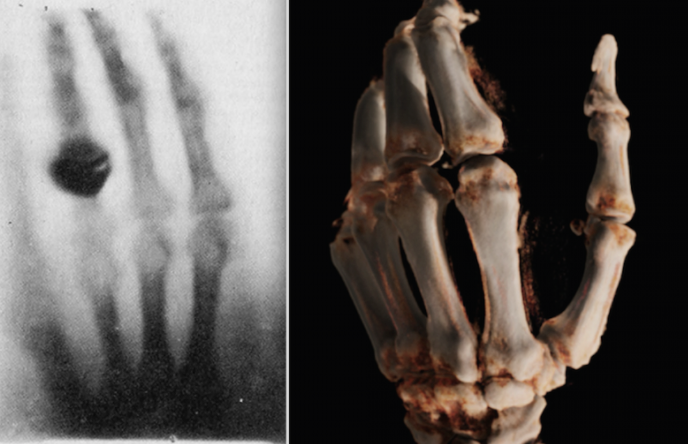

CT

X-Ray